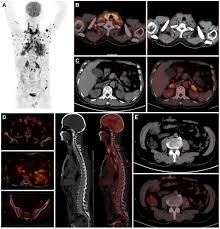

Stereotactic Body Radiation Therapy For Early Stage Non Small Cell Lung Cancer A Primer For Radiologists Radiographics from pubs.rsna.org Having copd may put you at risk for lung cancer and heart disease, among other conditions. This is because smoking complications can extend from lung tissue damage (emphysema) to lung cell damage (cancer). When cancer begins in the cells of the lung it is known as primary lung cancer. Various viruses, bacteria, and fungi can cause pneumonia. Lung cancer is a general term that includes all abnormal lung tissue cells that multiply unregulated and form tumors or growths in the lungs.these tumor cells may spread (metastasize) to other parts of the body.; In lung cancer, lung cells exhibit abnormal and uncontrolled growth starting the lungs, while asthma is caused by inflammation and/or mucus that decreases or blocks the breathing passages (bronchioles) of the lungs. Although slipping from emphysema to copd is usually not a drastic decline in health, early detection of lung cancer is critical for increasing your treatment options and improving your prognosis. Initial reports of an association between lung cancer and emphysema date back to the 1950s, when a report on 10 patients with congenital cystic pulmonary emphysema who died from primary lung cancer was published (4).